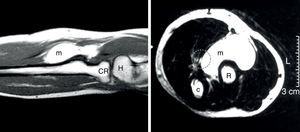

Se realizaron una ecografía de carpo comparativa, que fue rigurosamente normal, y una ecografía del codo y el antebrazo, que mostraba una masa fusiforme de 4,9×1,9cm, sin evidenciarse contacto con estructuras óseas, musculares ni tendinosas (fig. 1). Una RM demostró la presencia de una estructura que rodeaba anteriormente al tendón del bíceps de 5cm en sentido craneocaudal por 1,8 anteroposterior por 1cm en sentido transversal. La lesión presentaba un aumento de intensidad de la señal en las secuencias potenciadas en T1 y en T2, y suprimida en la secuencia de supresión grasa (fig. 2).

Resonancia magnética de antebrazo en T2. Izquierda: aspecto longitudinal donde se observa la masa anterior al radio. Derecha: corte transversal que demuestra la masa provocando un desplazamiento del área teórica por donde discurre el nervio mediano (circulo punteado). c: cúbito; CR: cabeza del radio; H: húmero; m: masa; R: radio.